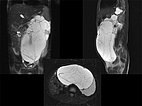

Die fettgesättigte, T2-gewichtete MRT in drei Schichtebenen zeigt die Ursache: Riesige Zysten retroperitoneal einer makrozystischen LM.